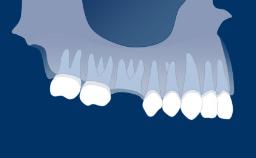

Once a tooth has been removed, dynamic physiological and dimensional changes take place during the healing phase that may influence the choice of the best time to place an implant.

These dimensional changes are clearly visible in the clinical situation of the site eight weeks after tooth extraction.